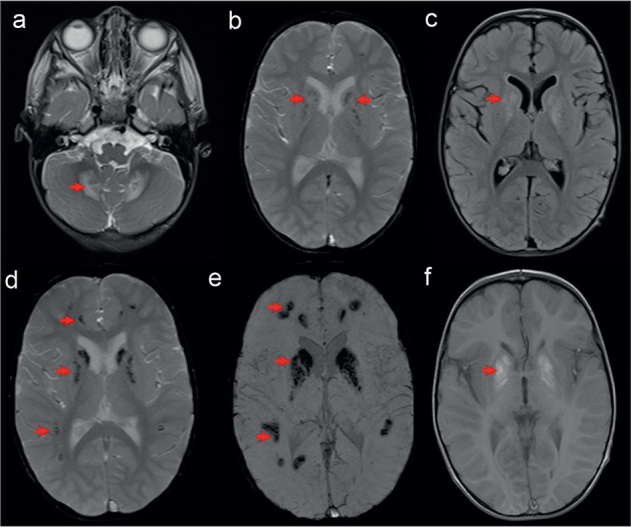

Case report: We report on the first COXPD21 patient with generalized tubular dysfunction and early childhood progression to chronic kidney disease (CKD). Thorough diagnostic evaluation was initiated at six months of age due to failure to thrive, muscular hypotonia, motor delay and recurrent bronchiolitis. The boy was lost to follow-up until the age of two years, when he was readmitted with elevated creatinine level, reduced estimated glomerular filtrate rate, normochromic anaemia, metabolic acidosis and hyperkalaemia. Urine abnormalities pointed to generalized tubular dysfunction. Two novel heterozygous missense variants in TARS2 gene were detected by the means of whole exome sequencing: c.1298T>G (p.Phe438Cys) of maternal origin and c.1931A>T (p.Asp644Val) of paternal origin. Currently, at 4.5 years of age, the boy has failure to thrive, severe motor and verbal delay and end stage of CKD. We referred the patient to paediatric centre that provides renal replacement therapy.

Conclusion: The overall clinical course in the patient we report on corresponds well to the previously reported cases of TARS2 related COXPD21, especially in regard to neurological and developmental aspects of the disease. However, we point out the generalized tubulopathy and early occurrence of CKD in our patient as atypical renal involvement in COXPD21. Additionally, this is the first report of hypothyroidism and hypoparathyroidism in a COXPD21 patient.